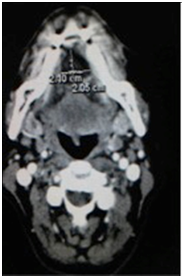

A 57-year-old Caucasian female was flown from a remote location to the emergency department for emergent consultation for a possible sublingual abscess. She complained of increasing right jaw pain and difficulty opening her jaw. The patient was afebrile and non-toxic appearing. Physical examination revealed right temporomandibular joint pain upon palpation, trismus, and slight fullness of the oral tongue and floor of the mouth. Initial laboratory data was within normal limits and was not significant for an acute inflammatory process. Computed tomography with intravenous contrast was performed and revealed a 2x3 centimeter intralingual hypodense fluid collection possibly representing an abscess (Figure 1). A trans-oral needle aspiration was performed to determine the nature of the cystic lesion. Approximately three cubic centimeters of yellow, thick, cheesy material was aspirated and sent for cytology. The patient was then discharged with a presumed diagnosis of dermoid cyst, dietary modifications for her temporomandibular joint syndrome, prophylactic oral clindamycin, and recommendation to return for surgical excision of the cyst. One week later, the patient returned to the emergency department complaining of increased swelling of the oral tongue and floor of mouth. The patient once again remained afebrile and non-toxic appearing. A repeat trans-oral needle aspiration revealed purulence and the patient was subsequently admitted to the hospital for intravenous ampicillin/sulbactam and scheduled for excision of the cyst at the next available operating time.

Figure 1(a-c) Pre-operative CT images with intravenous contrast demonstrating the intralingual fluid collection consistent with presumed abscess but post-operatively confirmed by pathology as a dermoid cyst.